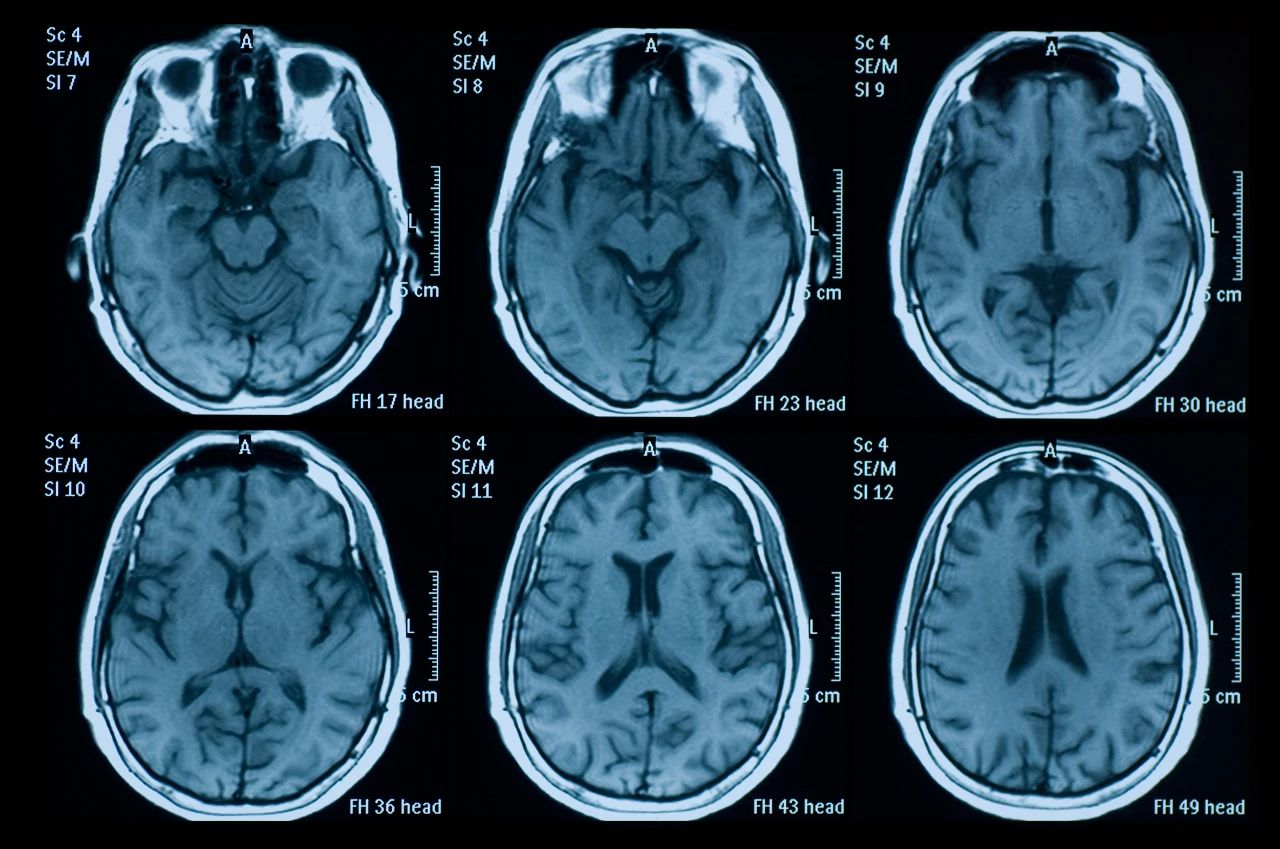

什么是創(chuàng)傷性腦損傷?

頭部受傷是頭部受到撞擊。它可能是輕微的,導(dǎo)致小腫塊或瘀傷,也可能更嚴(yán)重,導(dǎo)致腦損傷,如腦震蕩或腦出血。

而且到目前為止,尚無有效的藥物治療方法。值得注意的是,最近的研究表明干細(xì)胞療法的發(fā)展為腦損傷的治愈提供了可能。